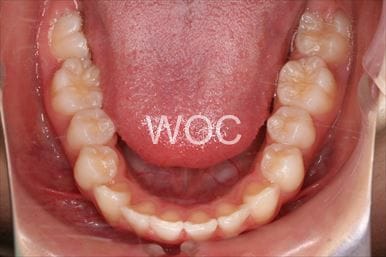

八重歯・叢生マウスピース型(カスタムメイド)矯正装置(インビザライン)

マウスピース型(カスタムメイド)矯正装置(インビザライン)を希望。ガタガタ(叢生)が強く上顎両側第一小臼歯抜歯か非抜歯のボーダーラインケースだったが、装置装着時間の協力も良く非抜歯で終了となりました。

- 年齢:35歳女性

- 主訴:ガタガタ

- 基本矯正料金:88万円

- 治療期間:2年6ヶ月

- 非抜歯

-